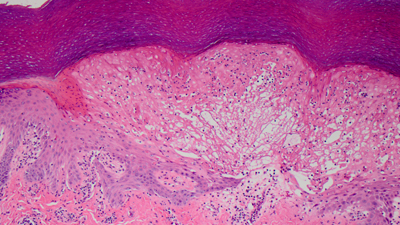

We are a National Outreach Laboratory of highly experienced practicing dermatopathologists dedicated to providing accurate diagnosis and quick turnaround.

Accurate, concise diagnoses delivered rapidly